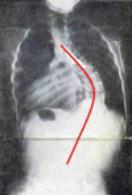

80-degree curvature

“In severe scoliosis — a curve greater than 70 degrees — the rib cage may press against the

lungs, making it more difficult to breathe."

"In very severe scoliosis — a curve greater than 100 degrees — injury to the lungs and the heart can

occur. The risk of lung infections and pneumonia increases.”

By age seven, my curvature had increased to 80 degrees.

In essence, as I grew, my upper body was folding in half.